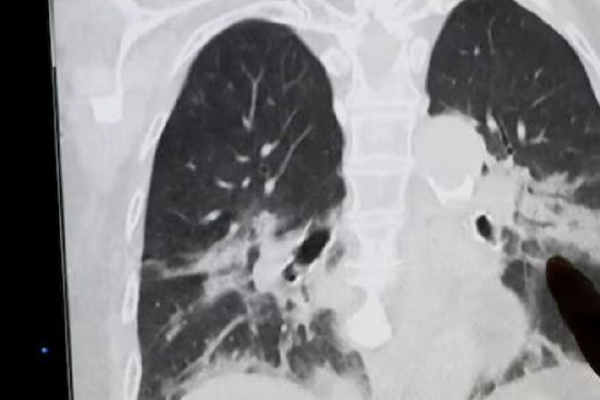

இதனால் குழந்தையின் உயிருக்கு ஆபத்து ஏற்படலாம் என அஞ்சியுள்ளனர் மருத்துவர்கள். அதானல் அல்ட்ரா சவுண்ட் ஸ்கேன் செய்து பார்த்ததில் குழந்தையின் வயிற்றுப்பகுதியில் கரு உருவாகி இருந்தது தெரியவந்துள்ளது.

அதில் குழந்தையின் வயிற்றுக்குள் பாதி வளர்ச்சியடைந்த இரட்டை கரு இருப்பதைக் கண்டறிந்தனர். கருவுக்குள் கரு இருப்பதே அரியவகை நிகழ்வு என்கிறது மருத்துவம்.ஆனால் இரட்டை கரு உருவாகி இருப்பது மருத்துவர்களை அதிர்ச்சியில் ஆழ்த்தி உள்ளது.

ஒரு வழியாக குழந்தையின் வயிற்றுக்குள்ளிருந்த இரட்டை கருக்களையும் மருத்துவர்கள் அறுவைசிகிச்சை மூலம் அகற்றி உள்ளனர்.

இதுகுறித்து குழந்தைக்கு சிகிச்சையளித்த மருத்துவர் கூறுகையில், ”அசாதாரணமான முறையில் குழந்தையின் வயிற்றுக்குள் இரட்டை குழந்தைகள் உருவாகி இருந்தன. இல்லாவிட்டால் அவை இரண்டுமே ஆரோக்கியமான குழந்தைகளாகவே பிறந்திருக்கும். குழந்தையின் வயிற்றுக்குள் கருவை கண்டதும் நாங்கள் ஆச்சர்யமடைந்தோம். ஆனால் அந்த கருக்கள் கற்பனை செய்யமுடியாத உருவத்தில் இருந்தன.

வயிற்றுக்குள் ஆரோக்கியமான கரு வளரும்போது, எங்கேனும் சற்று இடைவெளி இருந்தால் அந்த இடத்தில் மற்றொரு கரு புகுந்து ஆரோக்கியமான கருவுடன் சேர்ந்து வளரும். ஆனால் அவை முழுமையாக வளர்ச்சியடைவதில்லை. மேலும் அது உயிருடன் இருப்பதுமில்லை” என்று கூறியுள்ளார்.